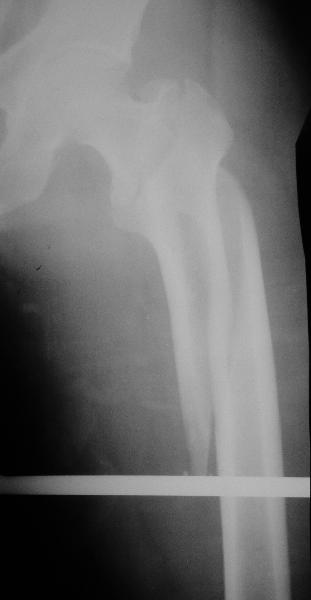

В диагноз пишем... Потом же как-то анализировать надо. Что-то никто не откликнулся на этот вопрос из англоязычных коллег. Все-таки - как такой перелом надо классифицировать? А если шейка бедра + диафиз? Завтра покажу такой случай.

Реконструкционный гвоздь.

Да, сейчас это и у нас самый напрашивающийся выбор. Сделали гвоздем ChM, картинки в приложении.